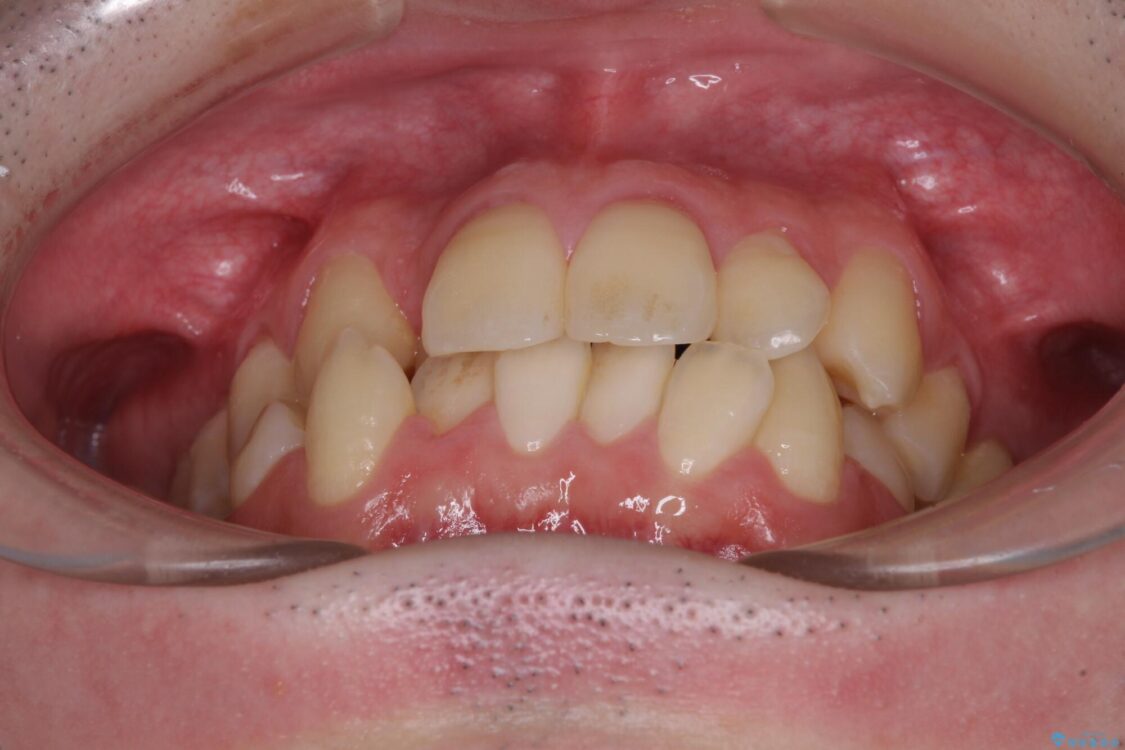

治療前

• 全顎的なクロスバイト 補助装置を用いてワイヤー矯正 治療前画像

八重歯や奥歯の噛みにくさを気にして来院された患者様です。

前歯のクロスバイトや八重歯の他に、左右最後臼歯のシザーズバイト(鋏状咬合)が認められました。